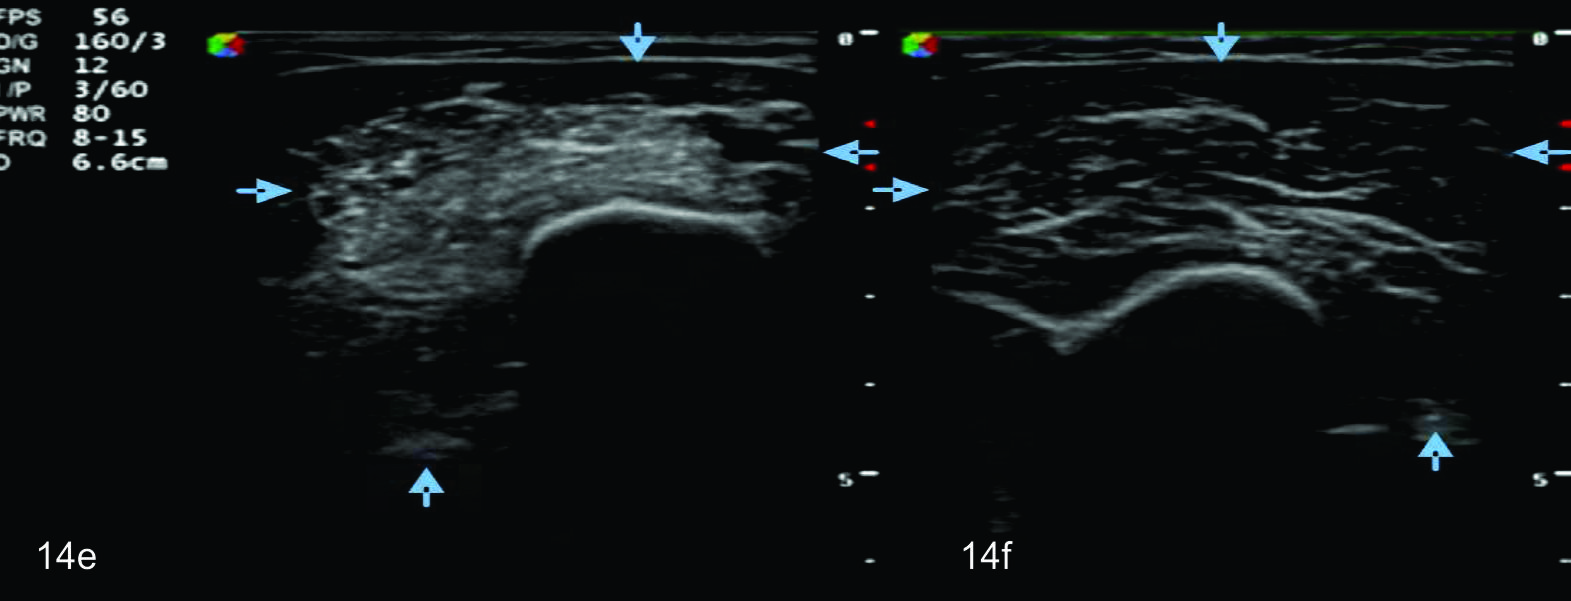

Figura 14 e, f, g y h

Lesión traumática del plexo braquial luego de accidente en moto.

EyF-Cortes comparativos a nivel de cara anterior de brazo derecho o afectado (E) y brazo izquierdo o sano (F), en donde se identifica la clara asimetría en el volumen y ecogenicidad de los planos musculares (flechas azules) en relación a cambios por atrofia. H- diáfisis humeral. GyH- Cortes comparativos a nivel de la cara anterior del antebrazo derecho o afectado (H) e izquierdo o sano (G), demuestra hallazgos similares. R- Diafisis radio, C- Diafisis cubito.